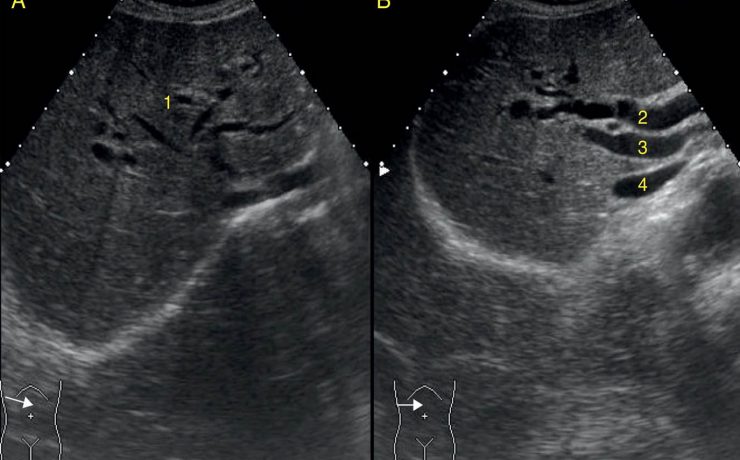

Alteraciones anatómicas de la vesícula biliar: duplicidad o vesícula tabicada o vesícula en gorro frigio.

De las anomalías congénitas de la vesícula biliar, la más frecuente es la vesícula en gorro frigio. Se produce a que una de las paredes forma un pliegue que produce una angulación del fundus. Se distingue en dos formas dos variedades: serosa y subserosa. En